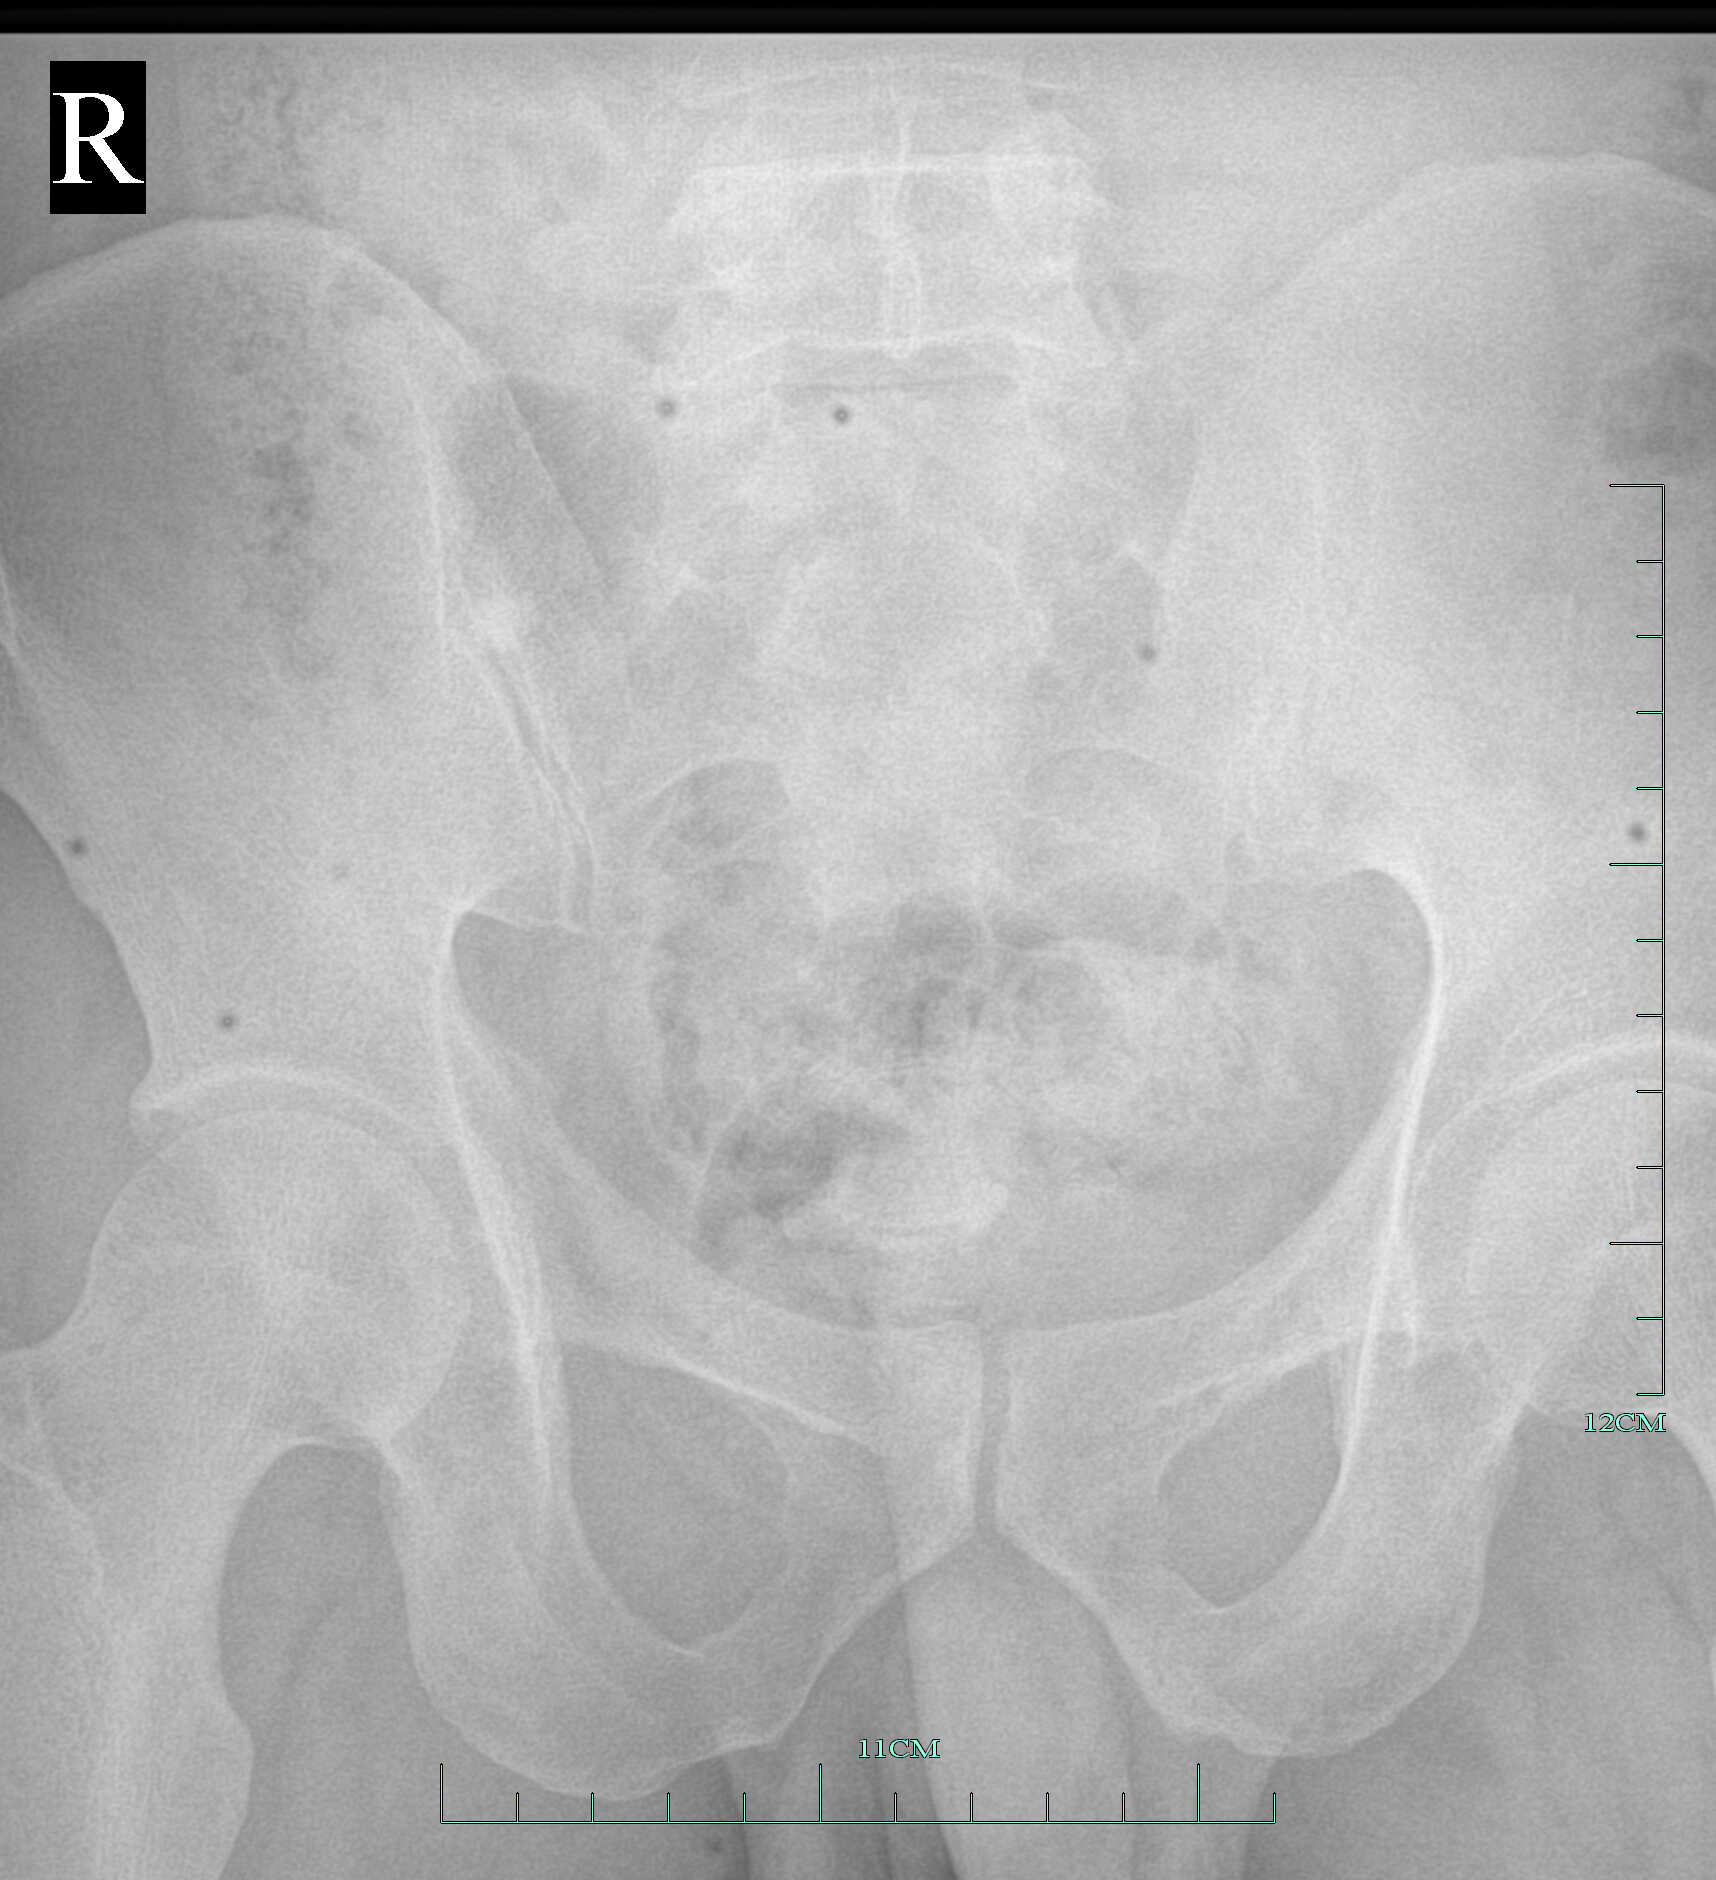

发张有坏点的平板DR片 骶尾椎0000.jpg